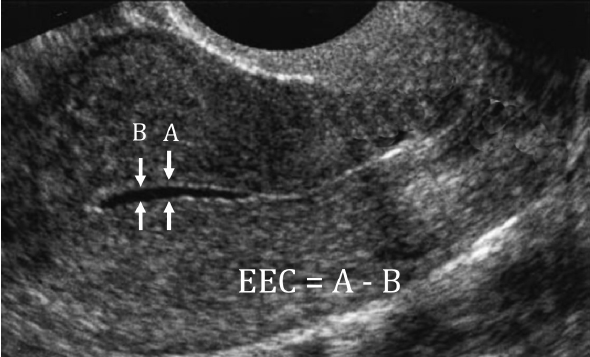

这个分型主要依据的是在B超(特别是阴道超声)下,子宫内膜的形态、厚度以及内膜与肌层交界线的清晰度。

• 超声表现: 外层两条亮线是子宫内膜的基底层,中间那条亮线是宫腔中线,三条线清晰可见。内膜本身回声比较低,看起来较暗。